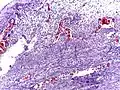

Pathology

Even for clinically certain appendicitis, routine histopathology examination of appendectomy specimens is of value for identifying unsuspected pathologies requiring further postoperative management.[69] Notably, appendix cancer is found incidentally in about 1% of appendectomy specimens.[70]

Pathology diagnosis of appendicitis can be made by detecting a neutrophilic infiltrate of the muscularis propria.

Periappendicitis (inflammation of tissues around the appendix) is often found in conjunction with other abdominal pathology.[71]